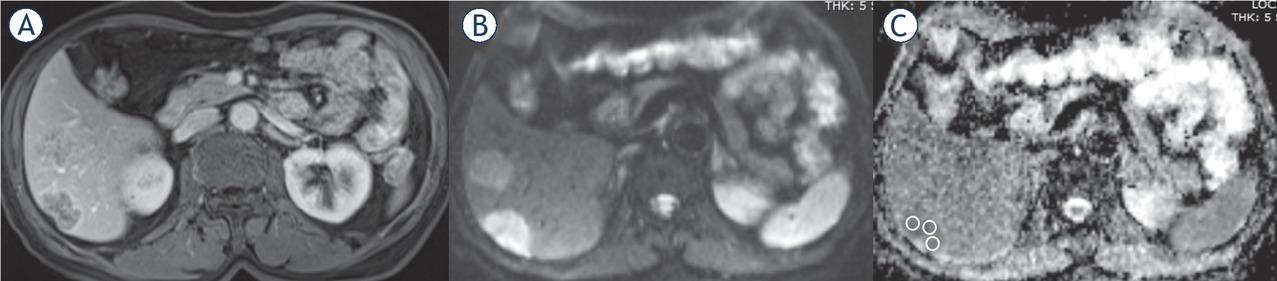

59-year-old male with liver metastases due to colorectal adenocarcinoma. Contrast-enhanced axial T1-weighted (T1W) (A), diffusion weighted image (DWI) obtained at b value of 800 s/mm2 (B) and apparent diffusion coefficient (ADC) maps (C) with free hand ROI placement technique.